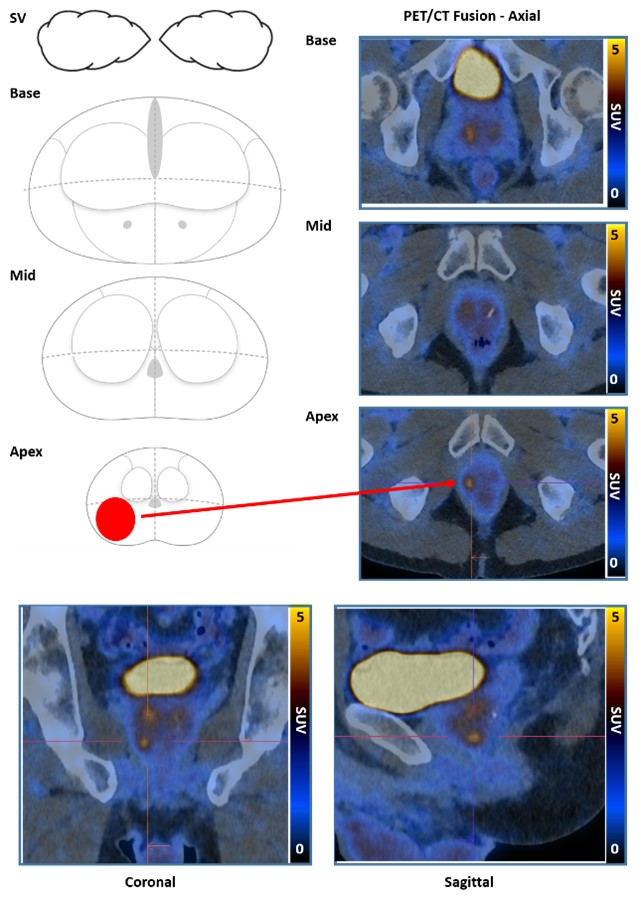

PRIMARY score

The PRIMARY score is a 5-category scale developed to identify clinically significant intraprostate malignancy (csPCa) on 68Ga-prostatespecific membrane antigen (PSMA) PET/CT (68Ga-PSMA PET) using a combination of anatomic site, pattern, and intensity.